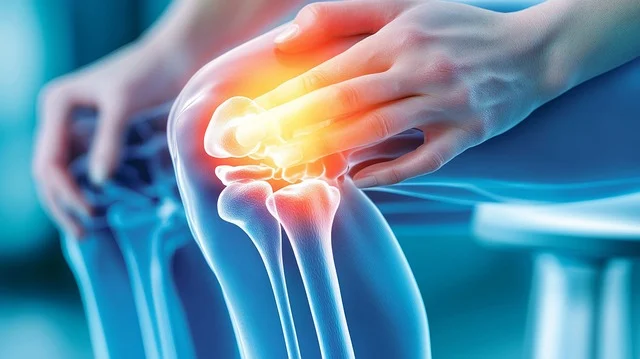

이번 포스트에서는무릎통증 원인 증상 총정리 하여 자히 알아보고, 이를 예방하고 관리하는 방법을 소개하고자 합니다. 아시다시피 무릎통증은 다양한 원인으로 발생할 수 있으며, 일상 생활에 큰 불편을 초래할 수 있습니다. 저도 무릎통증때문에 꽤나 고생한 적이 있었는데요. 무릎통증에 대한 올바른 이해는 효과적인 치료와 예방의 첫걸음이라고 생각합니다. 우리 같이 무릎통증 원인 과 증상에 대해 자세히 알아보도록 하시죠.

무릎통증 원인

무릎 통증원인 - 퇴행성 관절염 퇴행성 관절염은 나이가 들면서 발생하는 관절의 퇴행성 변화로 인해 무릎 통증을 유발합니다. 연골이 닳아 없어지면서 뼈와 뼈가 서로 마찰되어 통증과 염증을 일으킵니다.